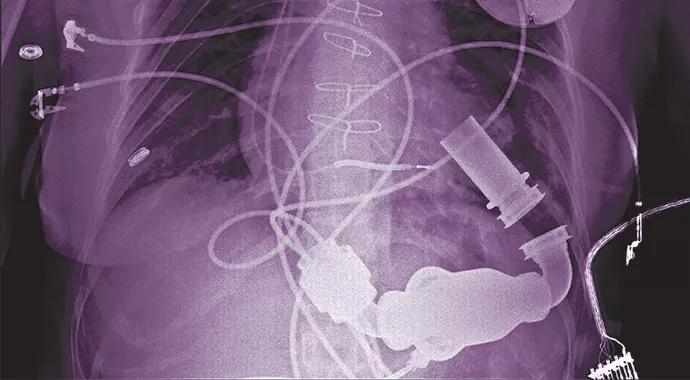

Left ventricular assist devices (LVADs) need not — and should not — be a therapy of last resort. If there’s one thing about mechanical circulatory support device therapy—of which LVADs represent the vast majority — that goes underappreciated among cardiovascular specialists, that’s it. So say Randall C. Starling, MD, MPH, and Nader Moazami, MD, the medical and surgical directors (respectively) of Cleveland Clinic’s Cardiac Transplantation and Ventricular Assist Device Therapy Program.

Use of LVADs for destination therapy—i.e., without plans for subsequent heart transplant—has increased in recent years, particularly as donor heart shortages have caused national heart transplant volumes to plateau around 2,200 annually. Yet that growth, which has brought the count of U.S. patients living with LVADs to 10,000 to 12,000, has barely made a dent in the population of 100,000 to 250,000 or more U.S. adults with advanced heart failure who stand to benefit from LVAD therapy.

Increasingly, what LVAD therapy means for patients is extended life and dramatically improved quality of life. Cleveland Clinic has seen its LVAD patients’ survival rates rise steadily in recent years (see table below) as its experience in implantation has deepened and as improved continuous-flow LVADs have displaced older pulsatile-flow device models.

And whereas the table includes all LVAD recipients—including bridge-to-transplant patients and destination therapy patients who receive LVADs as essentially a last resort—survival rates are considerably higher for patients who undergo LVAD destination therapy on a more elective basis. “Among those patients, our survival rates are close to 100 percent at one month and three months after LVAD placement,” Dr. Moazami notes.

To date, most experience with chronic LVAD therapy is in patients living with the devices for one to three years, though a small but growing population of patients have lived with LVAD support for five years or more. “Mechanical failure of LVAD pumps is very rare,” says Dr. Moazami. “Theoretically, these devices should be good to last for at least 10 to 15 years.”